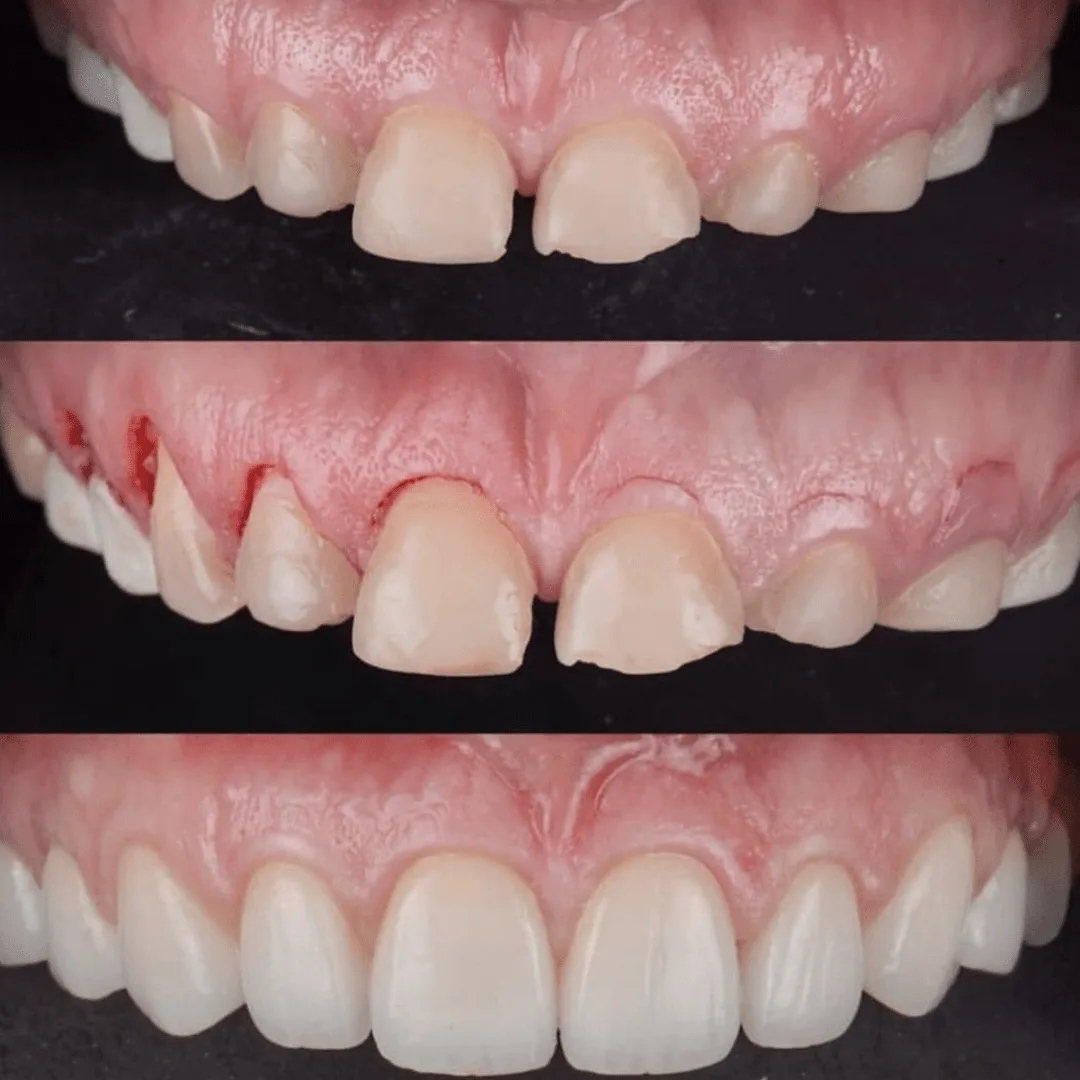

Patient presented to the office with a concern that the teeth were small and that too much gum shows when smiling. A comprehensive exam with x rays, pictures, smile analysis was done.

A detailed smile analysis with initial pictures, x rays, a scan of the teeth was used to fabricate a mock up smile.

A thorough aesthetic analysis was done and it was decided that the patient needed bigger teeth and gum contouring to compliment the facial anatomy.